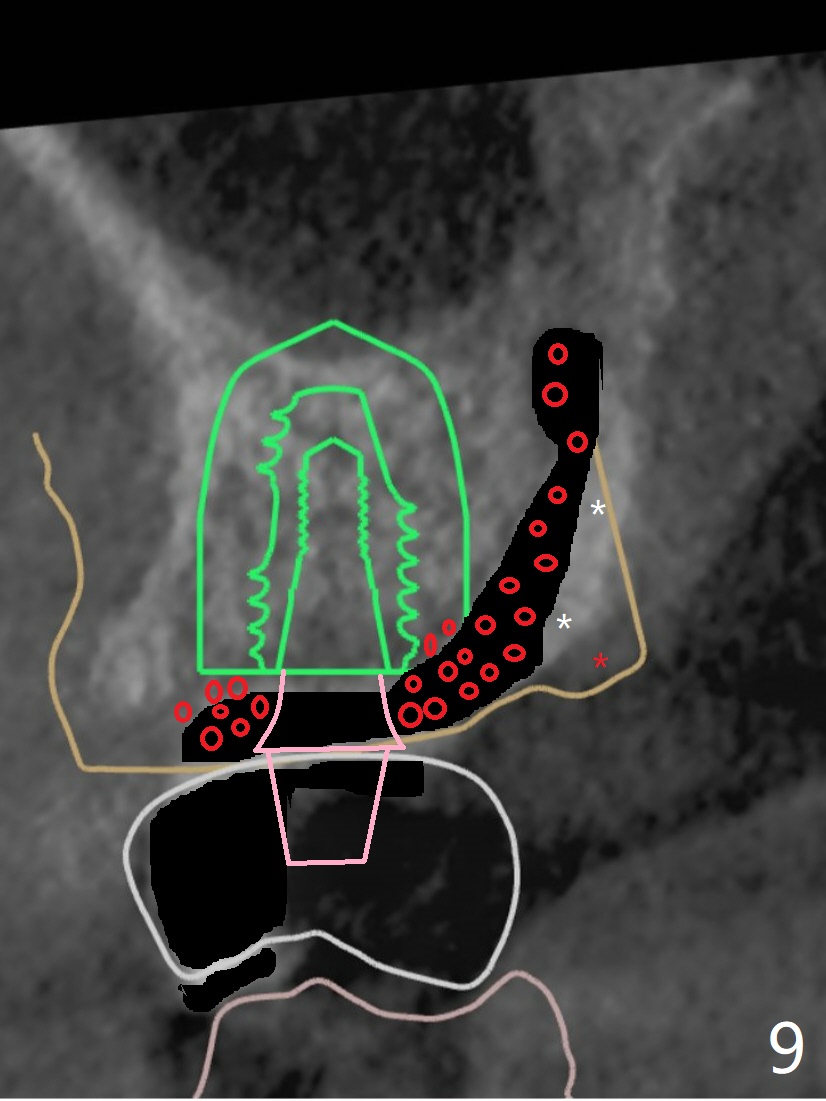

A coronal section shows the buccally-to-be-placed implant and the palatal root associated with apparent loss of the palatal plate (Fig.7). Socket shield (Fig.8 white *) will be done (black area) with bone graft (Fig.9 red circle) to reduce palatal implant thread exposure by keeping the palatal gingiva in place (red *). Pink: abutment.